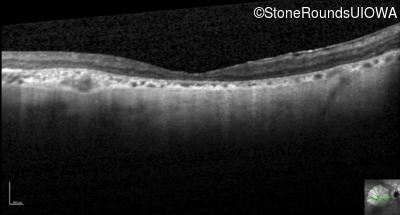

Optical Coherence Tomography - Left - 20/200 sc

Exemplar / OCT Stack

OCT Stack